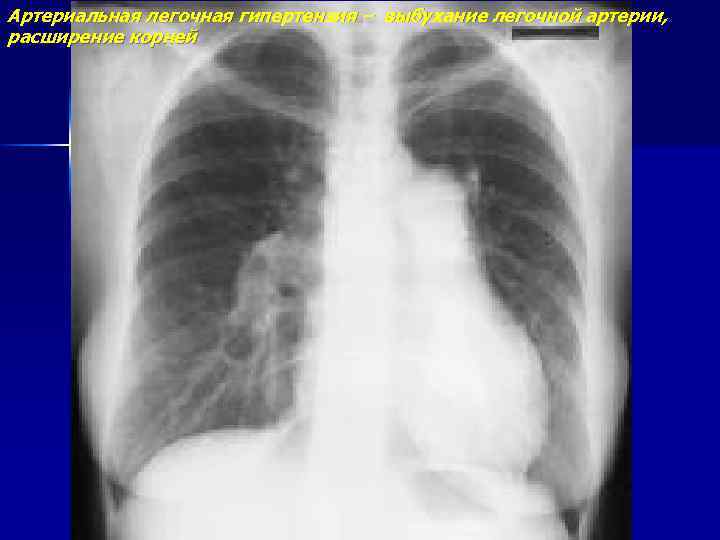

Артериальная легочная гипертензия – выбухание легочной артерии, расширение корней